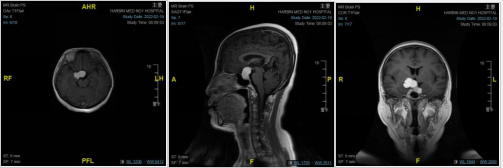

王宁了解病史完善相关检查诊断为巨大垂体腺瘤。由于患者肿瘤巨大,4厘米,上部向右侧生长,单纯经鼻内镜手术无法达到全切;下部有向海绵窦侵袭趋势,单纯开颅显微镜下手术亦无法达到直视下的安全完全切除。